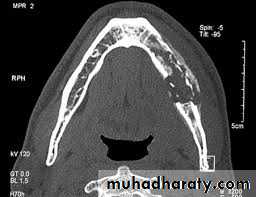

Computerized tomography (CT) scans have become the standard in evaluating maxillofacial pathology such as osteomyelitis. its sensitive in late stage when 30%-50% of the bone demineralized.

The clinical picture of ORN is most commonly seen with pain and exposed bone in the maxillofacial region ORN is more common in the mandible than in the maxilla . A dosage of radiation above 5,000 to 6,000 rads is generally felt to make the mandible susceptible to ORN. Radiographically, the appearance on the orthopantomogram or CT scan resembles conventional osteomyelitis with areas of osteolysis and bony sequestrum. Often there is an appearance of moth-eaten bone present on these films: treatment of ORN is aimed at removing the nonviable (necrotic) tissue and allowing the body to heal itself. Minor debridements of exposed bone and Current therapy of HBO consists of 100% oxygen delivered in a pressurized manner.